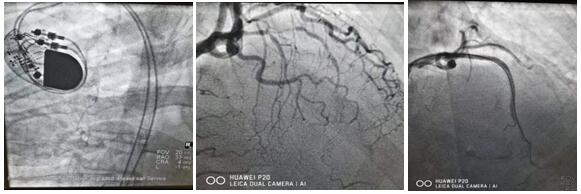

心脑血管疾病发病急,致死、致残率高。春节期间仅心血管病院介入团队就完成了46例急诊手术,挽救了46个家庭的幸福。建议防疫期间有问题及时咨询就诊,切不可因“疫”小病拖大病,增加家庭与社会负担。